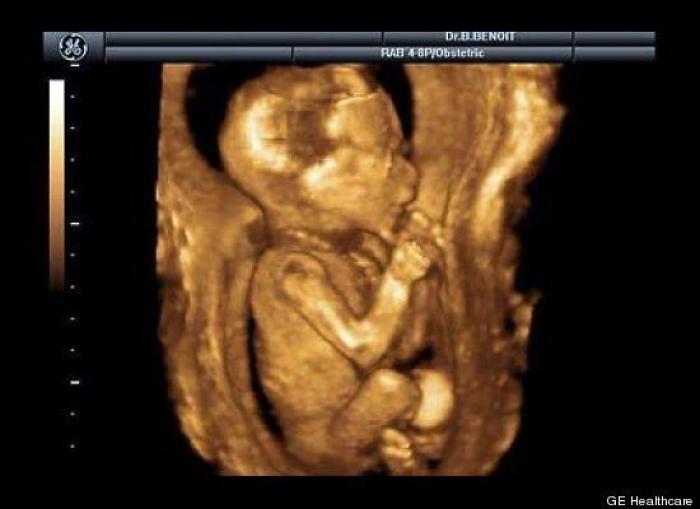

En esta galería puedes ver en fotos como es el desarrollo de un feto de semana en semana:

Desarrollo del feto, en fotos

Ver la galería